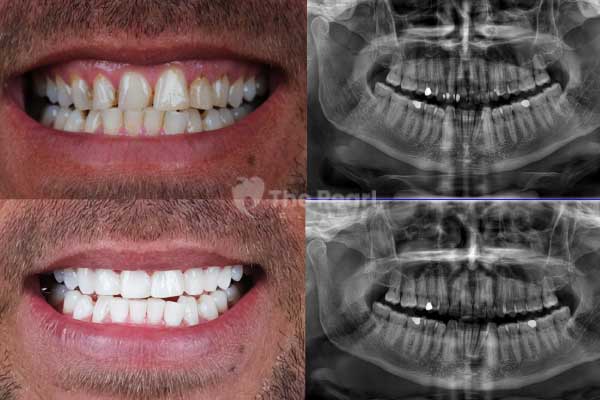

A filling, also known as a dental filling, is the most commonly used treatment method in the early stages of cavity treatment. It involves removing the affected tissue and leaving a space to be filled with a biocompatible material later. This process rehabilitates the damaged part of the tooth, restoring its functionality and original appearance.

There was a time when smiles were filled with silver and even gold decorations. In the past, highly durable silver amalgam materials were used. However, their negative aesthetic effects have led to the adoption of newer materials. Primarily, we refer to composites. These are a type of resin that matches the color of the bone like the tooth. As mentioned earlier, composites fill the void, and since they harden with light, they are cured with a special light.

The downside is that composites are less durable than metal fillings. However, this does not mean you have to change your fillings every week. During periodic check-ups, the dentist will tell the patient when the old filling needs to be replaced. Depending on the patient's care, bite, and other personal conditions, a composite filling can last for many years.